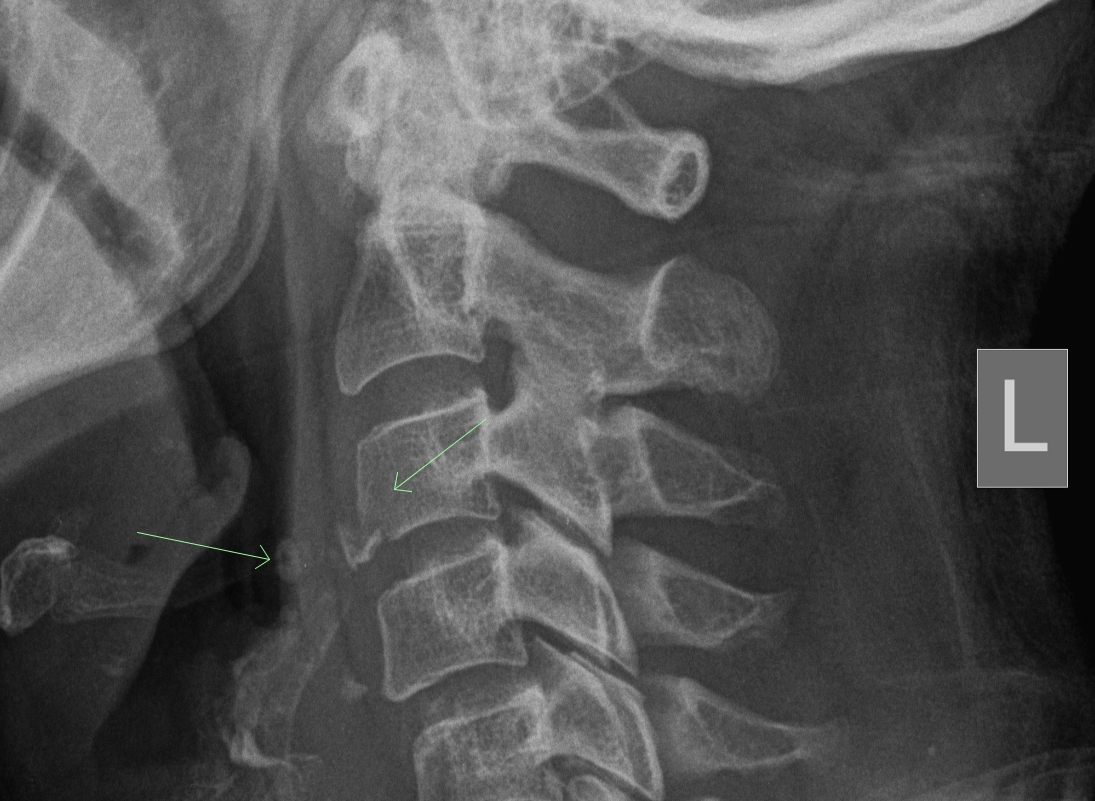

Purpose: The Canadian Cervical Spine Rules were developed in order to determine the need for radiographs after acute head/neck injury secondary to the risk of fracture.

If there is (1) High Risk Factors or (2) Low Risk Factors and the inability to actively rotate the neck > 45 degrees to the right and the left, radiographs are indicated.